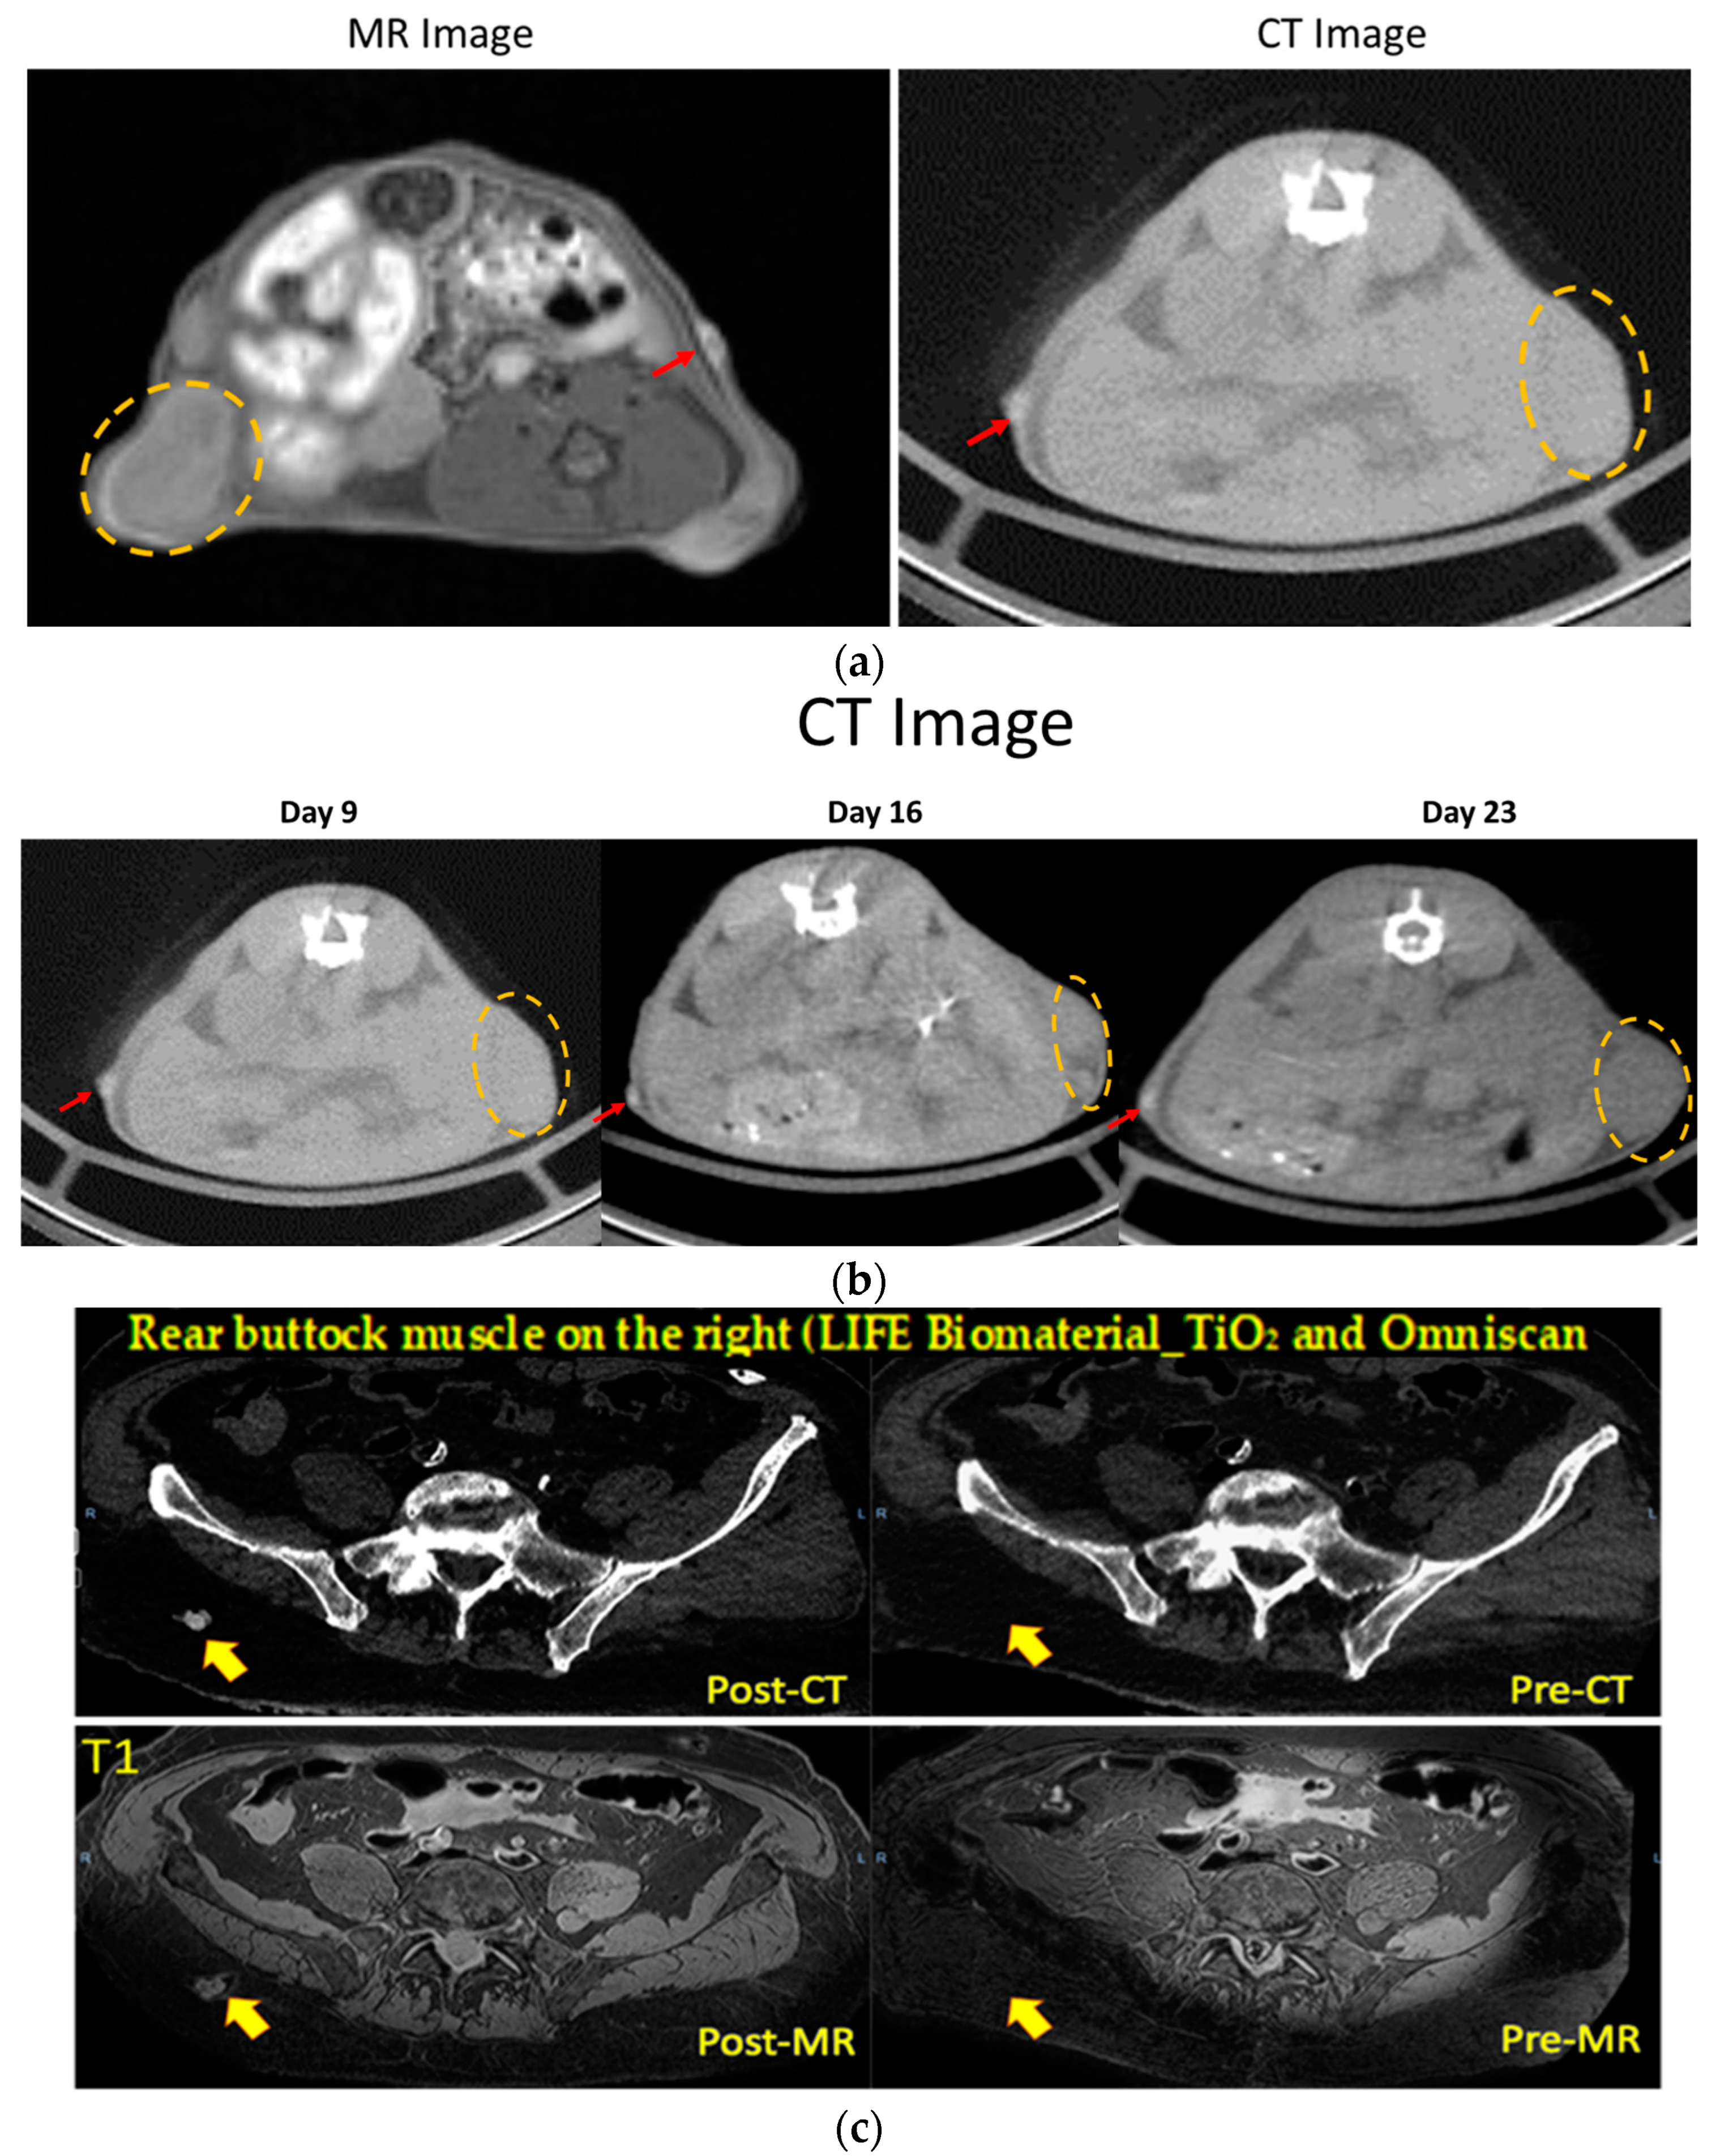

3.1. Potential of LIFE Biomaterial for Image-Guided Radiotherapy